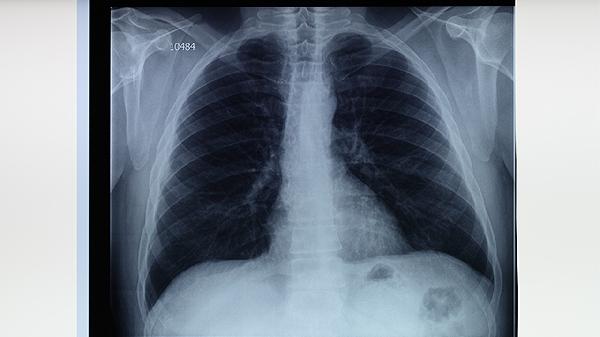

2、影像学检查选择

X光片可能漏诊早期病变,低剂量CT检出率更高。对于高危人群,建议直接选择增强CT。